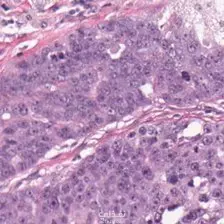

في هذا المشروع قمت بتطبيق دورة عمل كاملة لتعلم الآلة، بدءًا من تنظيف البيانات واستكشافها بصريًا وحتى بناء النماذج التنبؤية وتقييم أدائها لاكتشاف سرطان المبيض. استخدمت مكتبات Python الشهيرة مثل Scikit-learn وXGBoost وPandas و Tensorflow وkeras و , pytorch لتحليل البيانات وتطوير نماذج تصنيف وانحدار تحقق دقة تنبؤية عالية. ما قمت به: تنظيف البيانات والتعامل مع القيم المفقودة. تحليل استكشافي ومرئي للبيانات باستخدام Matplotlib وSeaborn. تدريب وتقييم نماذج تعلم آلي مختلفة (CNN, ResNet50, Inception ResNet, VGG16) تحسين النماذج للوصول لأفضل أداء ممكن. عرض النتائج بصريًا وتوضيح أهمية الخصائص. النتيجة: نموذج تعلم آلي متكامل يمكن الاعتماد عليه في التحليل التنبؤي والتطبيقات العملية فى اكتشاف سرطان المبيض.